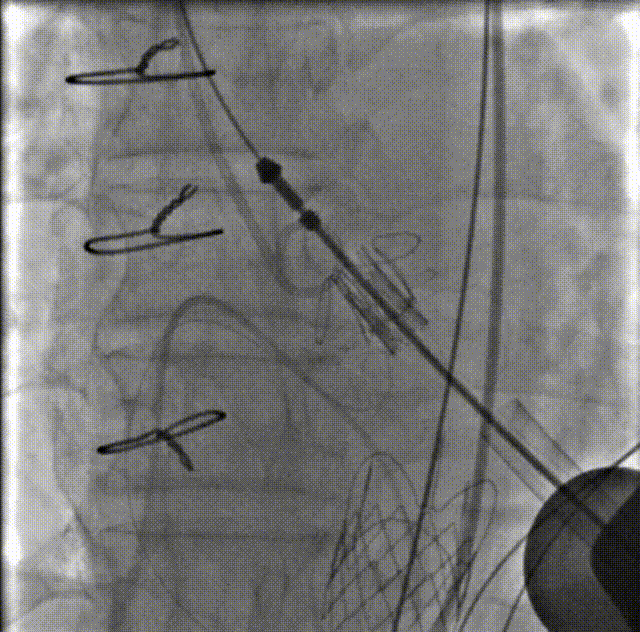

球囊后扩

二尖瓣入位